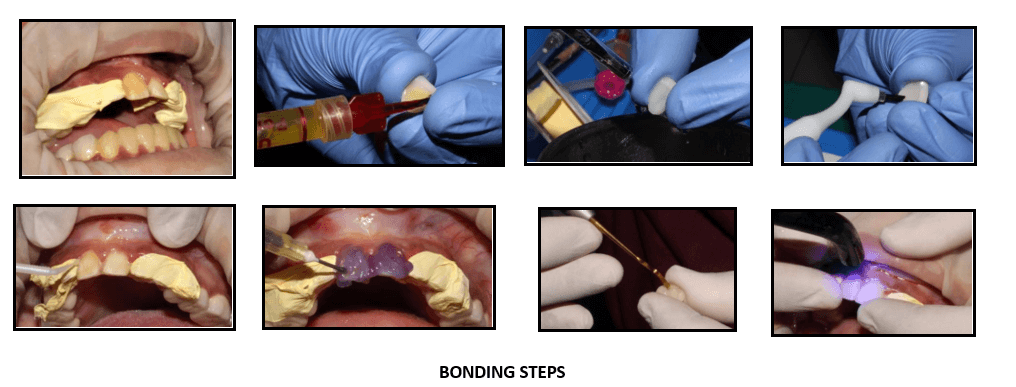

Calibra esthetic resin cement was used for the bonding of laminates.

Thoroughly clean all internal surfaces of the veneer with water spray and Etch the surface of the restoration with porcelain etch. Clean with water spray and dry.

Apply calibre silane to the Air dry the silanated surface of the restoration. Apply a single coat of Prime and bond NT adhesive to the internal surface of the veneer. Air dry for 5 sec. Light cure adhesive for 10 sec

Apply Prime & bond adhesive to tooth surface. The surface should remain wet for 20 sec. Gently air dry for 5 sec. light cure adhesive for 10

Dispense the desired calibra veneer Apply it on the veneer. Protect cement from exposure to light.

Seat the Tack the restoration in place by briefly light curing the gingival portion only for no more than 10 seconds. Remove excess cement.

Light cure all marginal areas for 20 seconds from each direction – buccal, lingual and interproximal

Removal of excess cement flash and finishing of the margins if